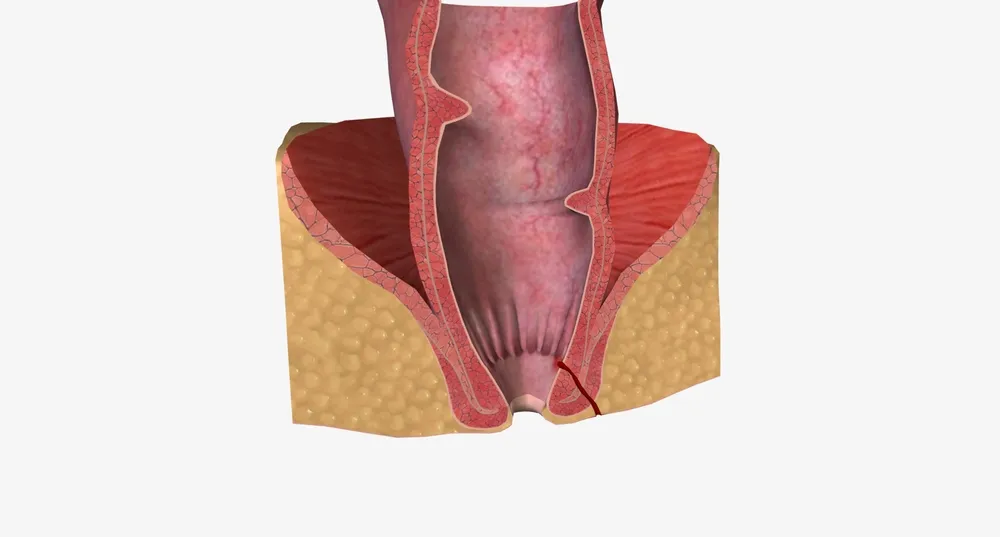

همه چیز درباره شقاق یا ترک مقعدی و راهکارهای درمانی آن

شقاق مقعدی یا فیشر آنال (Anal Fissure) یکی از شایعترین و دردناکترین بیماریهای ناحیه نشیمنگاهی است که بهصورت یک پارگی یا ترک طولی در دیواره داخلی کانال مقعدی ظاهر میشود. این آسیب اغلب در لایه پوششی مخاطی ناحیه انتهایی کانال آنال ایجاد میشود و میتواند با علائمی همچون درد سوزاننده، خونریزی، و اسپاسم عضلانی همراه باشد. گرچه شقاق در بیشتر موارد بدون مداخله جراحی و با درمانهای محافظهکارانه بهبود مییابد، اما در برخی بیماران ممکن است مزمن شده و نیاز به مداخلات تخصصیتر داشته باشد.

آناتومی و ناحیه درگیر در شقاق مقعدی

شقاق معمولاً در دیواره خلفی کانال آنال و در خط وسط ایجاد میشود؛ جایی که خونرسانی نسبتاً کمتر است و فشار در زمان دفع بالاتر میرود. در موارد نادر، شقاق ممکن است در قسمت قدامی یا در هر دو سمت همزمان دیده شود، بهویژه در بیمارانی که دچار بیماریهای زمینهای مانند کرون یا زخمهای ایمنی هستند. عمق ترک بسته به شدت آسیب، از یک خراش سطحی تا زخم عمیق با نمای بافت فیبروزه و پولیپ نگهبان متغیر است.

علائم شقاق یا فیشر مقعدی

علائم بالینی این بیماری معمولاً بسیار مشخص و آزاردهندهاند و شامل موارد زیر میشوند:

درد شدید و برنده در هنگام دفع مدفوع که ممکن است چندین دقیقه تا چند ساعت پس از دفع ادامه یابد.

خونریزی روشن بهصورت رگهای روی مدفوع یا قطراتی در توالت.

انقباض و اسپاسم عضله اسفنکتر داخلی که باعث تشدید درد و تاخیر در بهبود زخم میشود.